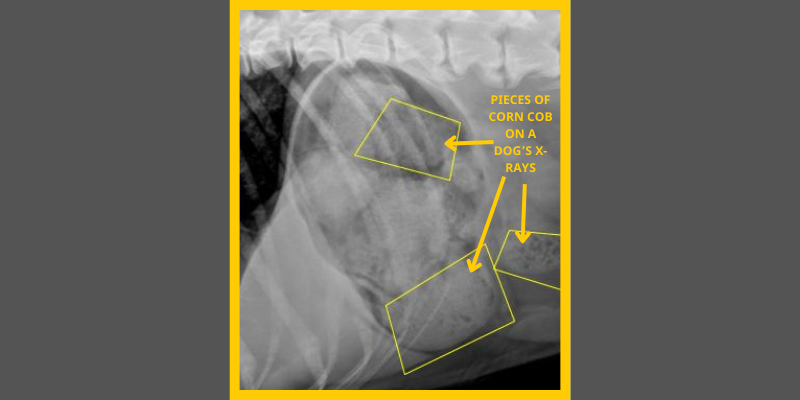

Note: These are not Finn’s x-rays but those of a different dog who also ate corn cob pieces

Although corn is safe for pets, the cob itself isn’t digestible. When pets like Finn swallow large chunks of corn cobs, they can cause a blockage in the stomach or small intestine. The blockage can lead to disrupted blood flow, resulting in systemic inflammation or infection, organ failure, and eventual death.

Once Finn arrived at our ER, we had an especially important mystery to solve: Were the corn cob pieces still in Finn’s stomach or were they lodged in his intestine?

However, if the cob pieces had moved into the small intestine, inducing vomiting would be dangerous. Inducing vomiting when a foreign body has moved into the small intestine can cause considerable damage to the intestinal lining or even perforate the bowel. Instead, Finn would need aggressive supportive care with IV fluids and anti-nausea medication to move the cob pieces into his colon for exit from his body via defecation. X-rays or an ultrasound would be needed to ensure all the pieces were expelled.

Our ER team induced vomiting. It took not one, but TWO doses of the medication before Finn finally relinquished his corn cob feast. (Labradors, amiright?) After several bouts of vomiting cob pieces, Finn went to imaging. X-rays showed little corn cob material left in Finn’s stomach and no pieces in his intestines. Emergency crisis averted!